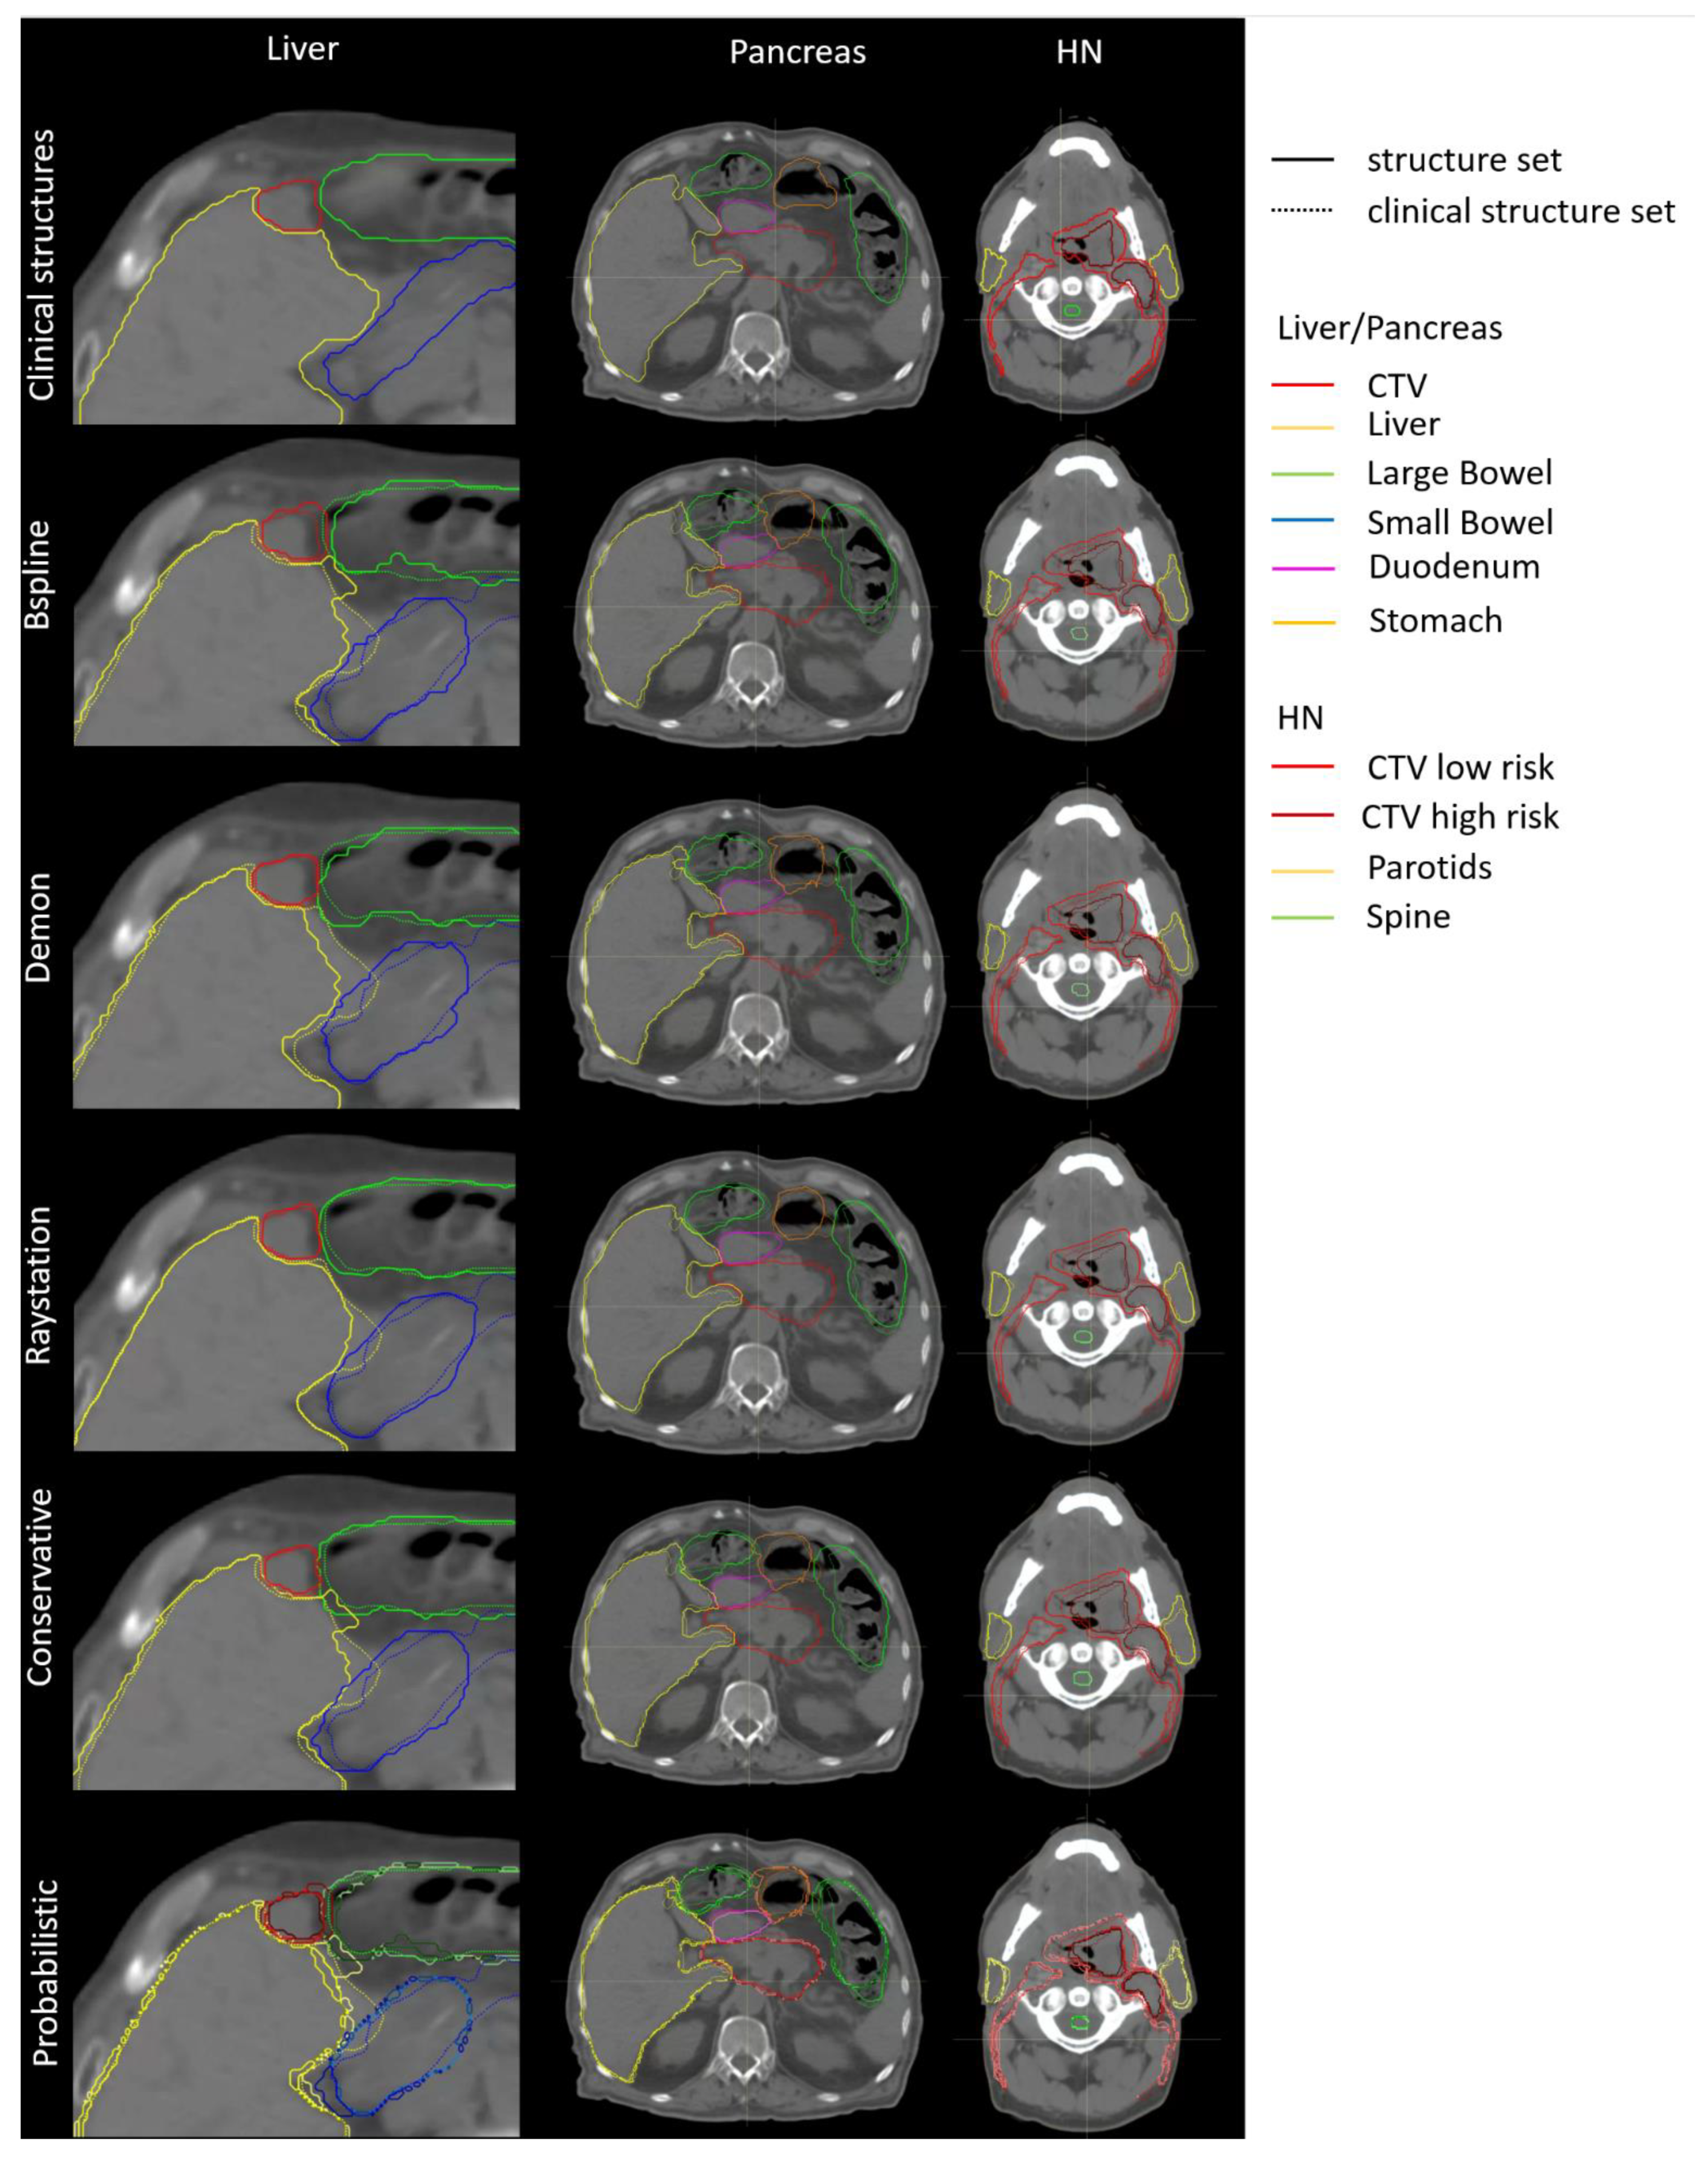

- Single-DIR adaptation:DIR-propagated structures were directly used for optimization without any manual corrections. Therefore, 3 different single-DIR adaptive plans were optimized on all replanning CTs, with structures deformed with Raystation, Plastimatch Demons, and Plastimatch B-spline.

- Multi-DIR adaptation:The same replanning CTs with the 3 different structure sets used for single-DIR adaptation described above were combined using the Raystation robust optimization function on multiple images and structure sets. This is the worst-case optimization [20], optimizing the plan using multiple images and structure sets in parallel.

- Conservative adaptation:Structures from the 3 different DIRs were combined. For pancreas and liver cancer patients, a stereotactic prescription was used, i.e., all organ constraints must be fulfilled, while target coverage is only the second priority. Therefore, for the conservative adaptation of these stereotactic prescriptions, the intersection of all propagated structures was used as the target structure, and the union for organs. In contrast, for HN patients with this prescription, the target coverage had a higher priority; therefore, the union of all propagated structures was used for the target and organs. The union and intersection of structures were calculated in Plastimatch and imported into Raystation for optimization.

- Probabilistic adaptation:Substructures were defined for each structure depending on how often a voxel was classified as part of the structure. If all 3 DIRs agreed that a voxel was a target, this voxel was included in the 100%-target substructure; if only two DIRs classified a voxel as a target, it belonged to the 67%-target substructure; if only one algorithm defined it as a target, it belonged to the 33%-target substructure. The 100%, 67%, and 33% substructures were calculated in Plastimatch and imported into Raystation. The optimization constraints of each structure were identical to those used for the planning CT, but the weights of these substructures varied according to the frequency that voxels were classified as a target or organ amongst the DIRs [21].

- Reference adaptation:All replanning CTs had “clinical” structures, manually contoured by a physician. These structures were directly used for the optimization of reference adaptive plans. These reference adaptive plans should result in the best possible treatment plan.